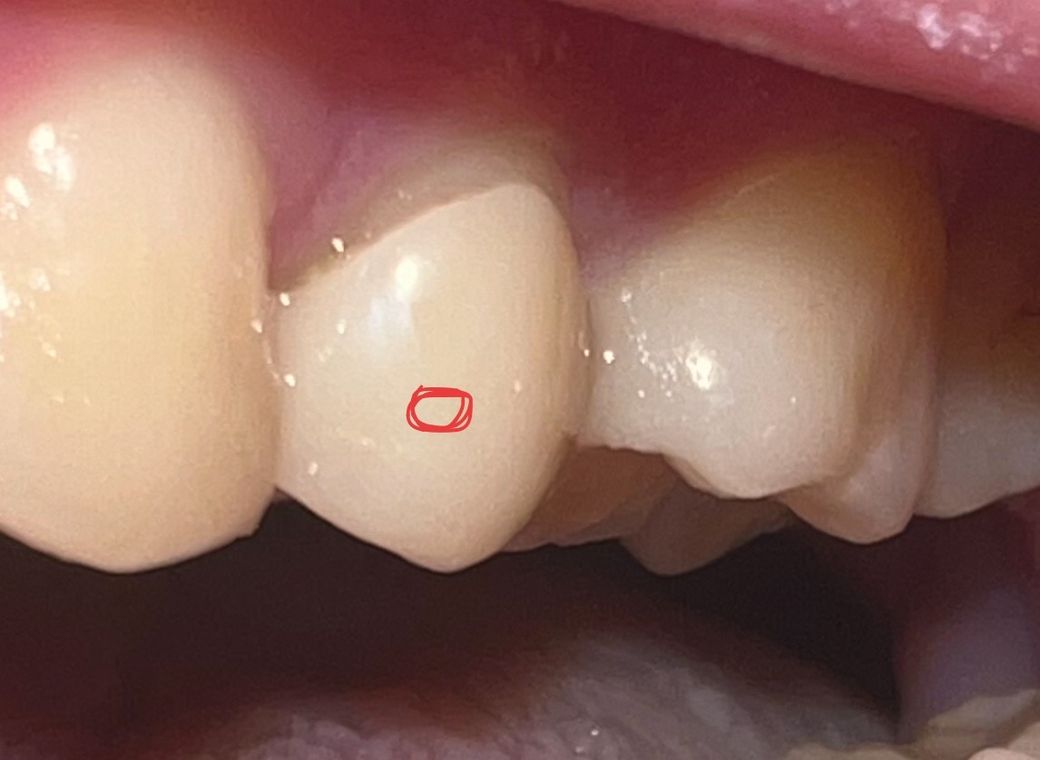

빨간색동그라미 부분이 신경치료후 크라운을 한건데 보시면 너무 제 자연치아가 보이는거같아서요… 노화로인한 잇몸퇴축이라기엔 아직 20살이고 관리진짜 열심히합니다… 애초에 씌울때부터 잘못된건가요 ?

아니면 잇몸건강을위해 좀 띄워 놓은건가요?

치아와 보철물 경계를 마진이라고 하며 마진을 치아와 잇몸 딱 경계부에 두는 경우도 있고(equi), 어떤 목적이나 이유 때문에 잇몸과 떨어뜨려서 상부에 두는 경우(supra)도 있습니다. 처음 상태가 어땠는지 모르니 단정지을 순 없습니다.

현재로서는 치료 전의 사진을 보아야 합니다. 잘못되었다기 보다는 보철물의 끝 부분을 치은연상(잇몸 위)에 두는지, 치은연하(잇몸 아래)에 두는지 등은 상태에 따라 다를 수 있습니다. 대부분은 치은연하에 두지만 불가피한 경우에는 치은연상에 둘 수 있으며 그러한 경우에는 지금처럼 보일 수 있습니다. 현재로서는 치료한 치과를 방문하여 문의해보는 것이 필요합니다.